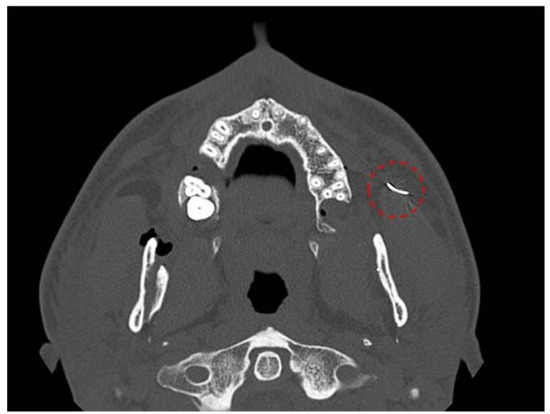

| Patient 3 | 32, M | Syringe needle | Right pterygopalatine space, medial pterygoid muscle | None | 0 | INT | Transoral | 130 | C-Arm X-ray | Lingual Nerve | FB Extracted | NR |